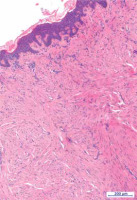

Figure 2

Histopathological examination of the lesion confirmed the diagnosis of piloleiomyoma; intersecting, well-differentiated smooth muscle bundles composed of spindle cells with no atypia, elongated nuclei and eosinophilic cytoplasm. Proliferation seen here is poorly circumscribed. Some of cells are enlarged and hyperchromatic, similar to those seen in uterine leiomyomas (hematoxylin and eosin stain, 7.22× magnification)